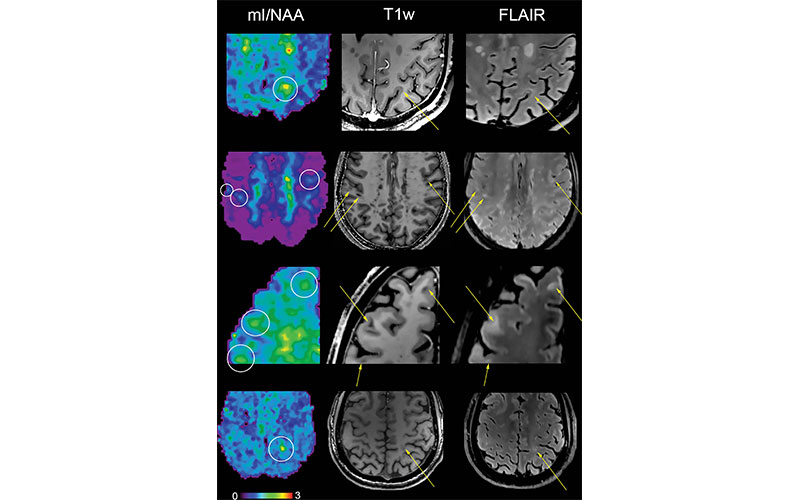

An advanced imaging technique known as proton MR spectroscopy is a promising tool in this effort. MR spectroscopy of the brain can detect several metabolites that have potential relevance for MS.

The results showed reduced levels of an amino acid derivative called N-acetylaspartate (NAA) in patients with MS. Lower levels of NAA have been linked to impaired integrity of neurons in the brain. People with MS also showed elevated levels of myo-inositol (MI), a compound involved in cell signaling. Higher levels are indicative of substantial inflammatory disease activity.

The metabolic alterations in normal-appearing white matter and cortical gray matter were associated with disability.

Researchers said the results show a potential role for 7T MR spectroscopic imaging in visualizing MS pathology beyond demyelinating lesions.

“MRI of neurochemicals enables the detection of changes in the brain of multiple sclerosis patients in regions that appear inconspicuous on conventional MRI,” said study senior author Wolfgang Bogner, PhD, from the High Field MR Centre at the Medical University of Vienna in Vienna, Austria. “The visualized changes in neurochemistry of normal-appearing brain tissue correlated with the patients’ disabilities.”